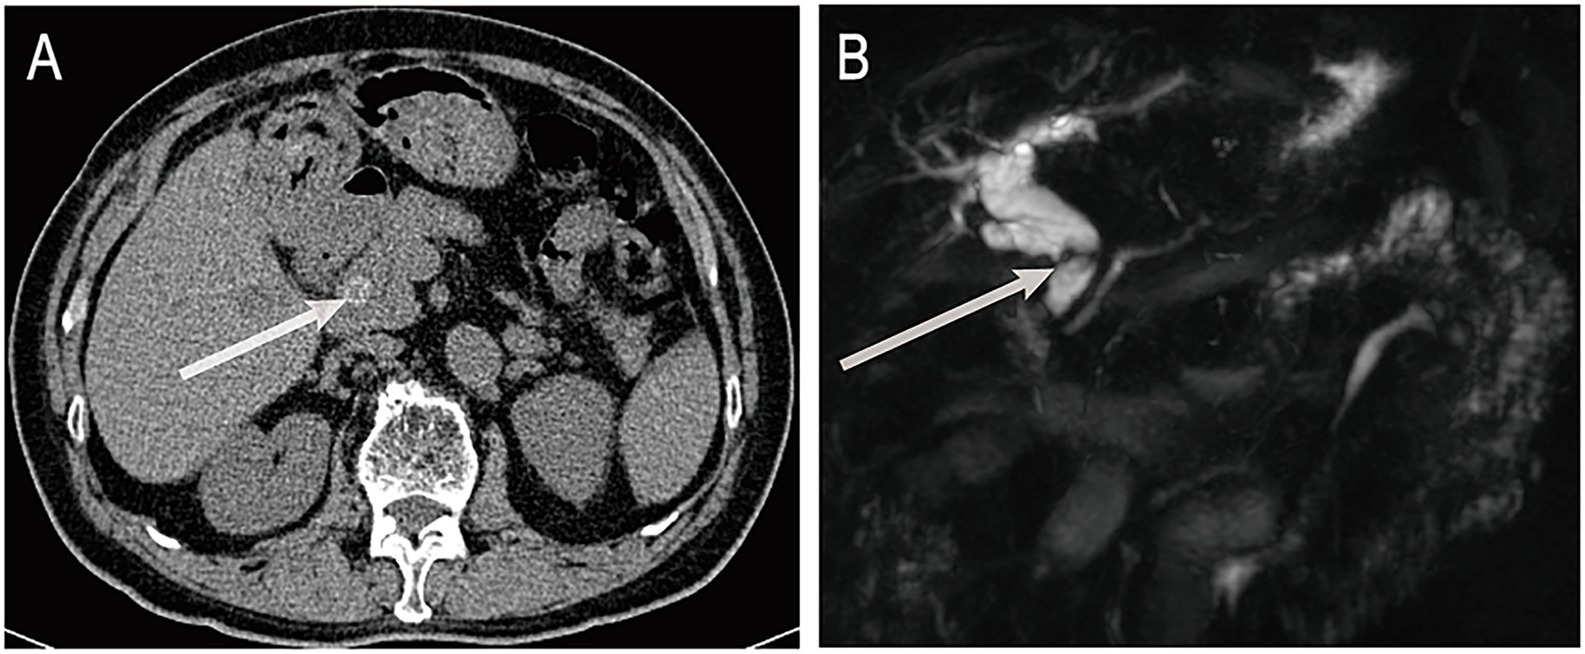

A 72-year-old male was admitted on June 16, 2025, with a 3-day history of fever. His medical history included cholecystectomy, previous ERCP, and chronic obstructive pulmonary disease. On admission, his body temperature was 38.8 °C, accompanied by cough without significant sputum production or abdominal pain. Laboratory tests revealed a neutrophil ratio of 92.1% and an absolute neutrophil count of 8.49 × 109/L. Blood cultures were positive for Escherichia coli. Liver function tests showed a total bilirubin level of 45.9 μmol/L, direct bilirubin of 33.1 μmol/L, and indirect bilirubin of 12.8 μmol/L. Aspartate aminotransferase was elevated to 259 U/L and alanine aminotransferase to 161 U/L. Abdominal computed tomography (CT) revealed choledocholithiasis and biliary obstruction (Figure 1A). Magnetic resonance cholangiopancreatography (MRCP), including non-contrast and contrast-enhanced sequences, demonstrated intra- and extrahepatic bile duct dilation, common bile duct stones, and reduced enhancement of the left hepatic lobe, consistent with biliary infection (Figure 1B).

Figure 1

(A) Abdominal non-contrast CT shows a stone in the distal common bile duct. (B) MRCP reveals dilatation of intrahepatic and extrahepatic bile ducts with distal obstruction caused by a stone. ERCP, endoscopic retrograde cholangiopancreatography; CT, computed tomography; MRCP, magnetic resonance cholangiopancreatography. The white arrows indicate bile duct stones.